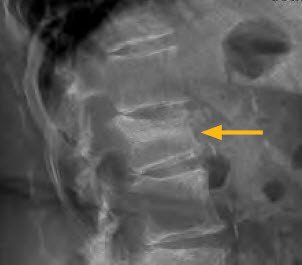

Nach drei Wochen stärkster Schmerzen meldete der Ehemann die Patientin bei uns an. In einem ersten Schritt wurden die Muskeln, Sehnen und Gelenke sorgfältig abgetastet. Die Beckenuntersuchung gestaltete sich schmerzfrei. Zum Erstaunen der Patientin zeigten sich sogenannte funktionsgestörte Wirbelgelenke sowie verspannte Muskeln im oberen Bereich der Lendenwirbelsäule, also an einem Ort des Körpers, an dem sie gar keinen Schmerz gespürt hatte. Durch diese Erkenntnis erweiterte man die Diagnostik um eine einfache Röntgenuntersuchung des Rückens. Die Befunde waren eindeutig, die Diagnose klar: Es handelte sich um einen gebrochenen ersten Lendenwirbel, der seinerseits Schmerzausstrahlungen bis ins Becken verursachte (Abb. 1).

Der Übergang zwischen Lenden- und Brustwirbelsäule ist eine biomechanische Schwachstelle. Diese Region ist äusseren Belastungen besonders stark ausgesetzt, weshalb die Wirbel des sogenannten thorakolumbalen Übergangs die bei Frakturen am häufigsten betroffenen Wirbelkörper darstellen. Der hautversorgende Anteil der dazugehörigen Nerven versorgt die Bezirke der unteren Lendenwirbelsäule, des oberen Gesässes sowie der Leiste und der seitlichen Hüftgegend (Abb. 2).

Die erwähnten anatomischen Zusammenhänge erklären somit Beckenschmerzen bei einem Wirbelkörperbruch wie im oberen Fall beschrieben.